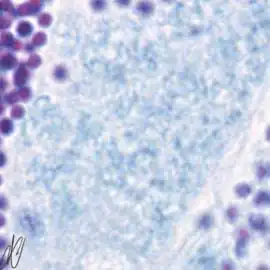

spermatogenesiscysts with successive stages of spermatogenesis in a seminiferous tubule | |||

| H&E | Putt's carbol fuchsin as a marker of spermatogenic maturation |

1. spermatogonium A (SgA) [arrows]: large single cell, with a large hypochromatic nucleus; early spermatogenic stages do not stain with Putt's carbol fuchsin. SgA divides mitotically to renew itself and to produce: |

2. early spermatogonium B (eSgB) [arrows]: morphologically indistinct from SgA, appears in clusters of 2-4 cells. Note a single Sertoli cell [red arrows], which are only occasionally observed; on the other hand, Sertoli cells are prominent after exposure to androgen or anti-androgen. |

3. early spermatogonium B (eSgB) [arrows in left image]: morphologically indistinct from SgA, appears in clusters of 2-4 cells; there is moderate mitotic activity in spermatogonium B, as indicated by PCNA immunostaining [arrows in right image]; in contrast, there is only very light PCNA immunostaining in the single spermatogonium A cell [red arrows in right image]. Early SgB divide mitotically to produce: |

4. late spermatogonium B: smaller than early SgB, clusters >4 cells [arrows in left image]; there is high mitotic activity, as indicated by the strong PCNA immunoreactivity [arrows in right image]. |

5. late spermatogonium B: clusters >4 cells [arrows]. Late SgB divides to yield smaller primary spermatocytes. Primary spermatocytes undergo meiosis, which consists of DNA duplication (yielding tetraploid cells: two copies of each chromosome, each copy consisting of two sister chromatids), genetic recombination, and two maturation divisions. The product of the first maturation division are secundary spermatocytes (diploid: one copy of each pair of chromosomes, consisting of two sister chromatids), the second maturation division yields spermatids (haploid). The first maturation division takes days, and therefore the successive stages of this division can easily be discerned: |

6. spermatocyte, leptotene stage of meiotic prophase ("threadlike" appearance of chromosomes). |

7. spermatocyte, leptotene stage of meiotic prophase, progressing to the zygotene stage; Note that there is staining with Putt's carbol fuchsin from this stage on, although still faint here. |

8. spermatocyte, zygotene stage of meiotic prophase ("bouquet" configuration of chromosomes) |

9. spermatocyte, zygotene stage of meiotic prophase ("umbrella" configuration of chromosomes). |

10. pachytene primary spermatocytes; in this stage, there is longitudinal contraction of the chromosomes, and the chromatin strands have a coarse appearance. |

11. dividing primary spermatocytes (diplotene stage); the metaphase, anaphase, and telophase of the first meiotic division (respectively equatorial arrangement of chromosomes, movement to cell poles, and actual division of the cell) are completed quickly, and are therefore only present briefly. The daughter cells of the first meiotic division are known as secundary spermatocytes (diploid). The second meiotic division is also completed quickly, and therefore secundary spermocytes are neither easily discernible. The resulting cells of the second meiotic division are: |

12. spermatids (haploid). |

13. spermatids. |

14. mature spermatozoa are released from open spermatocysts into the lumen of the tubules (spermiation). |